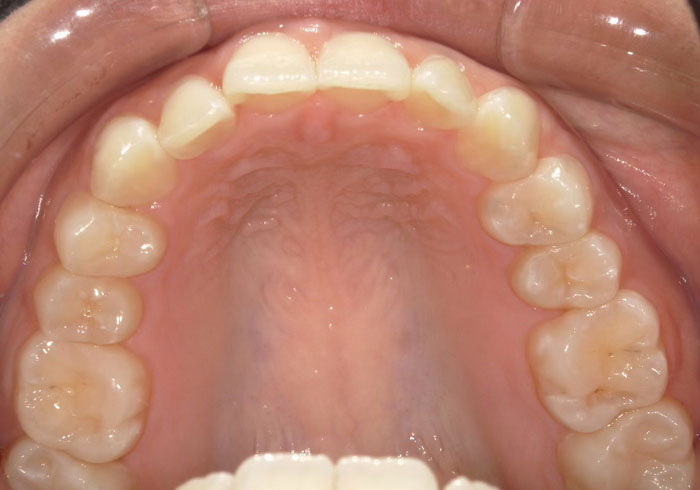

口腔内写真

治療後

マウスピース矯正 マウスピース矯正 マウスピース矯正